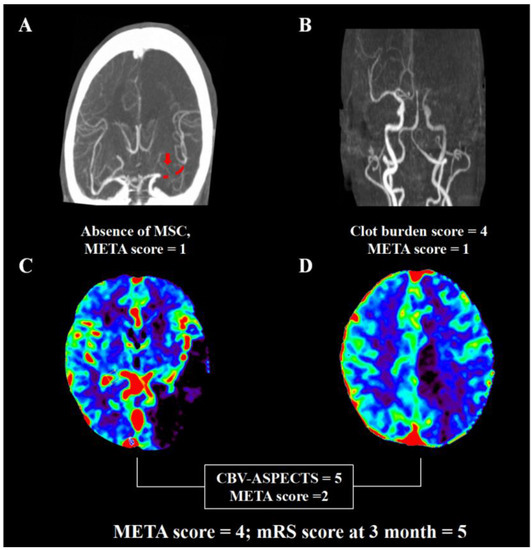

The AUC of the META score was higher than other previously established prediction scales including the PRE score, THRIVE score, and any single component in the META score (Figure 1). The risk of poor outcome increased with a higher META score (0 = 35.9%, 1 = 47.9%, 2 = 60.0%, 3 = 73.3%, 4 = 80.6%, and 5 = 100%; p < 0.001). Representative images of multi-mode imaging in META are shown in Figure 2.

Figure 2. Representative images for calculation of META. A male patient had occlusion of left middle cerebral artery on dynamic computed tomography angiography (A,B). He had clot burden score of 4 (occlusion of M1 and M2), one segment of clot (red dot that the red arrow points to, (A)), good collateral with >50% filling of the occluded middle cerebral artery territory (A). Cerebral blood volume map (C,D) demonstrated the Alberta Stroke Program early CT score of 5. Thus, the META score was 4. The modified Rankin score was 5 at 3 months despite successful recanalization.